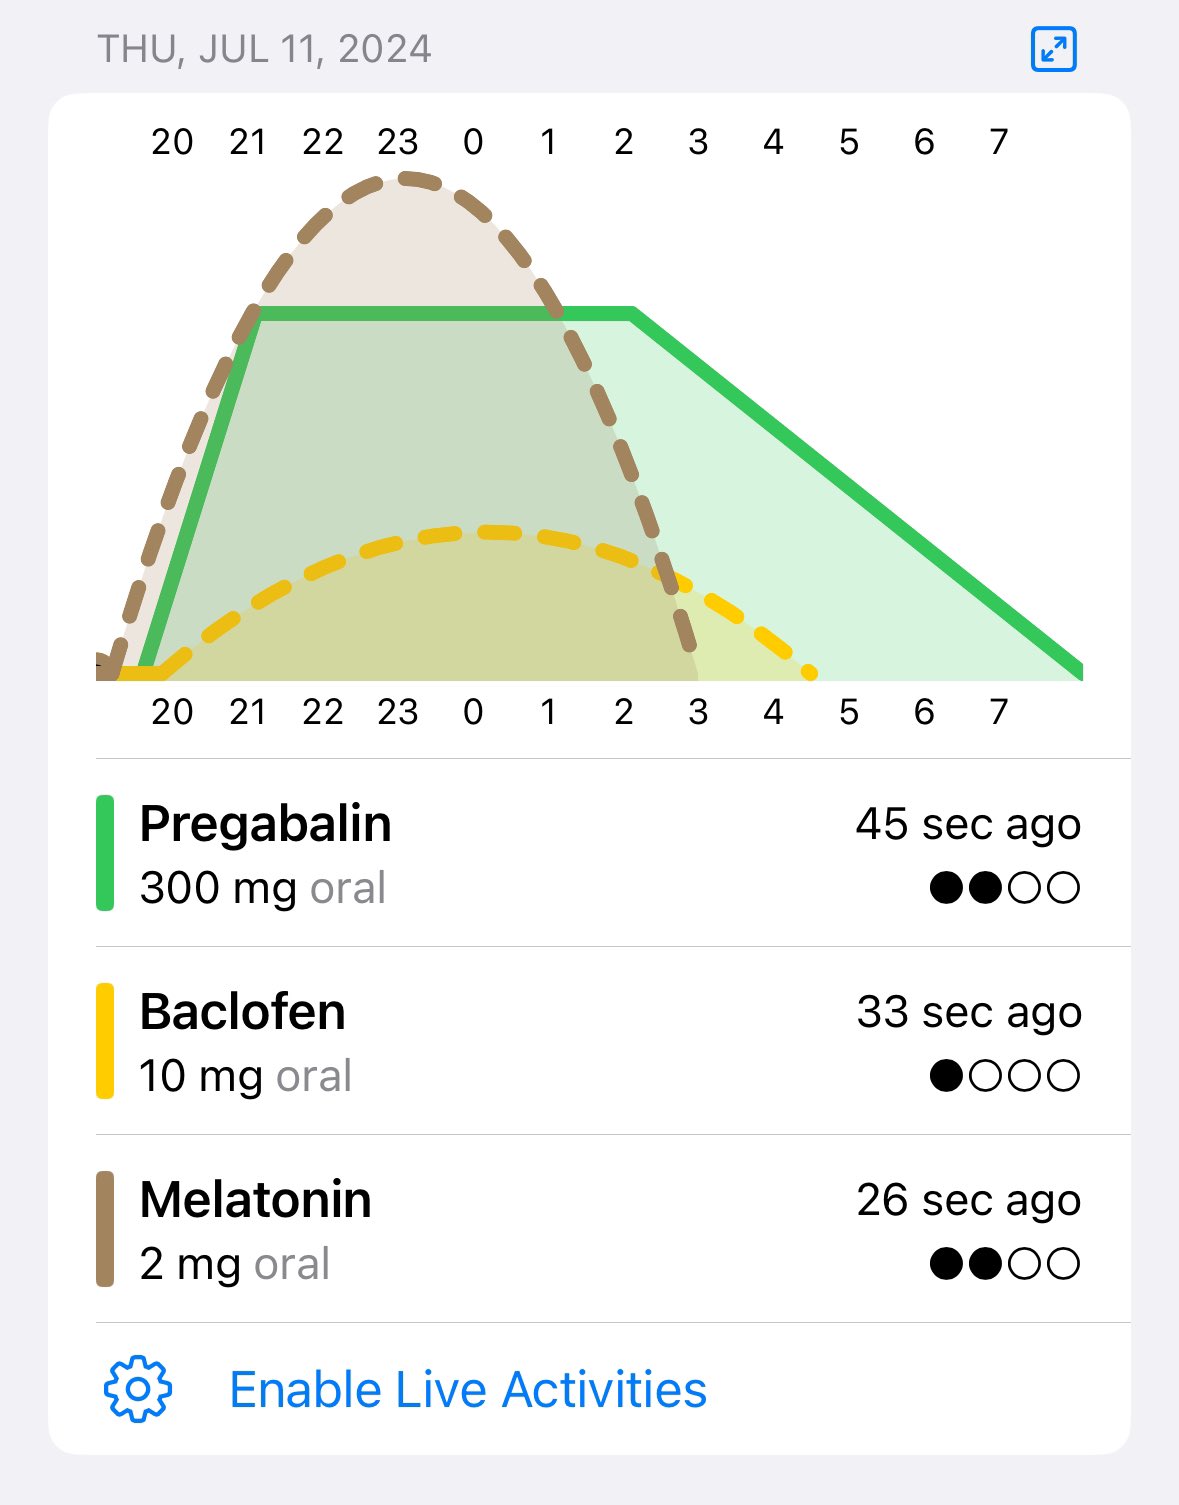

甚至在第二天有余晖的感觉,虽然发生了很多破事但没怎么影响心情*抗焦虑&镇静

运动协调性稍差,表现为走路和站立时平衡不好

此剂量下对睡眠的改善作用,增加了慢波睡眠且没有影响rem,精力恢复+

FDA数据,在临床剂量下(75-600mg)普瑞巴林的依赖性低于bzd,并相比之下它产生的认知和精神运动障碍较轻 https://t.co/TJ7ZOQ7pbC